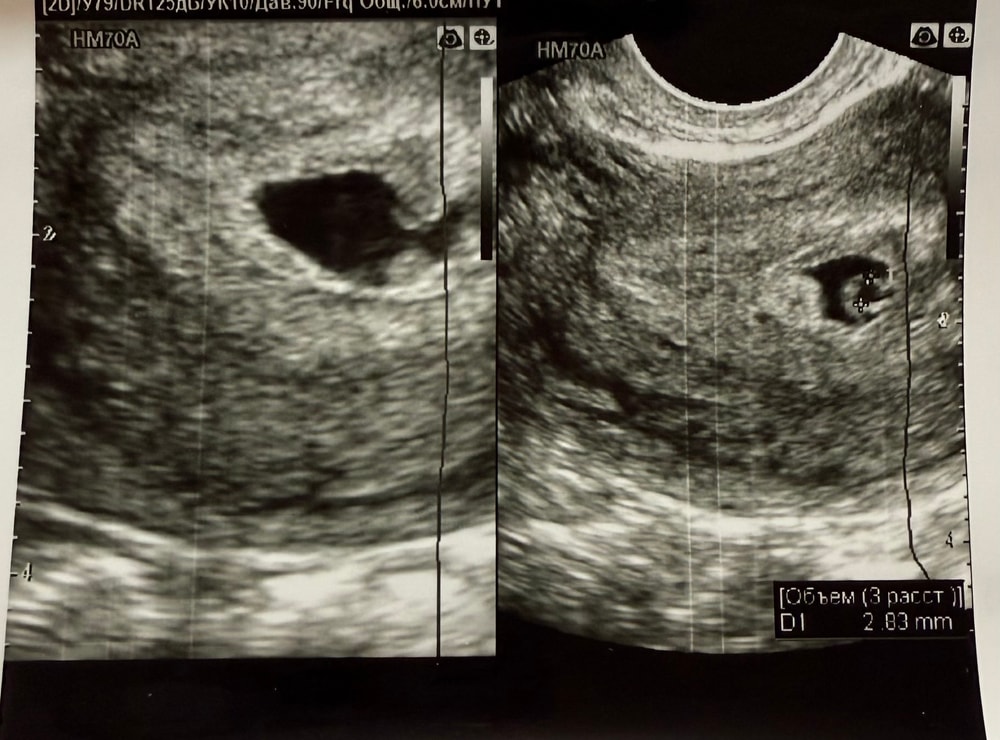

Я хотела бы уточнить информацию по поводу результатов УЗИ. На первом УЗИ, которое было проведено на сроке шесть недель и пять дней, мне указали размер желточного мешка — 2,8 мм, и приложили снимок. Однако на втором УЗИ, сделанном ровно на семь недель в жк, было написано, что желточный мешок не определяется.(снимка нету)

Не могли бы вы помочь мне разобраться в этой ситуации? Я не вижу желточный мешок на снимке УЗИ и задумываюсь, могла ли врач ошибиться в своих выводах. Так же нашли ретрохориальную гематому. Сказали на узи есть отслойка и деформировано плодное яйцо.

Ну и эмбрион не определяется, один узист поставили анэмбрионию и сказал, что за три дня плодное яйцо усохло с 10 мм на 9 мм. В комментарии приложила узи. И почему две фотографии на узи что это?